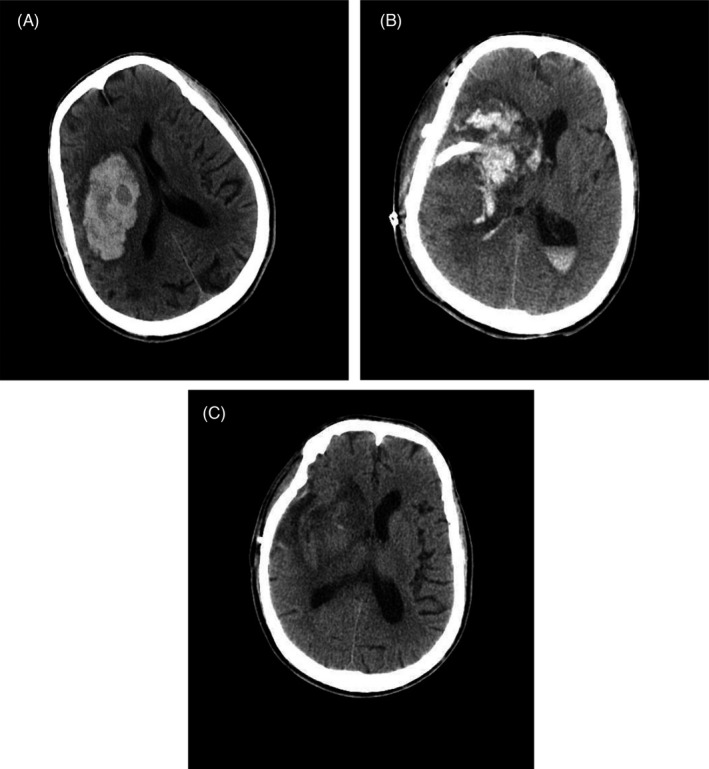

Computed tomography (CT) scan showed postoperative rebleeding at the right basal ganglia.

FIGURE 1.

Cranial CT examination. Cranial (A), (B), and (C) CT images of the head showed preoperative, admission, and discharge intracranial conditions, respectively